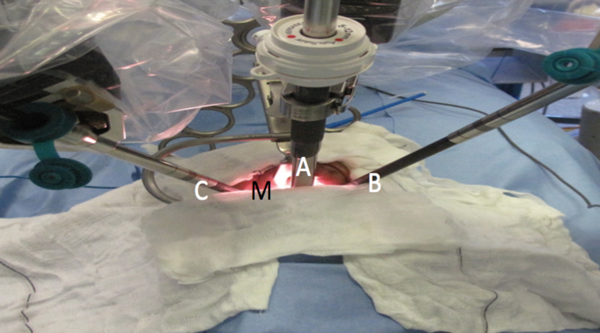

The patient is positioned supine with a shoulder roll and head ring. Nasotracheal intubation is performed when possible to permit unrestricted and clear access to the tongue base and epiglottis during surgery. St Mary’s TORS set-up is shown in Figure 1.

Figure 1: TORS set-up using the standard da Vinci system.

A = 30° up 8 or 12mm dual channel endoscope;

B = 273µm thulium laser; C = 5mm long tip Maryland dissector; M = patient’s mouth.